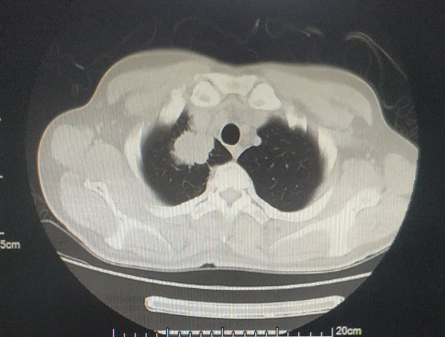

福建省肿瘤医院始终扮演着我省抗癌工作的坚强堡垒角色,并为肿瘤病人提供综合治疗,兜底全省的疑难重症癌症病人诊治工作。近年,医院强化技术创新,建立了各种肿瘤多学科诊疗的技术体系和全疾病周期的健康管理,针对每个病人的不同病情制定个体化诊疗策略,有机地在病人的不同治疗阶段合理使用,最大程度提高远期疗效,同时保障病人的生活质量,延长晚期病人生存期,使更多不可治的肿瘤得到可治。初步统计,2022年相关数据显示,在外院抗肿瘤治疗后转诊至该院进一步治疗的疑难病人治愈及好转率达 45.85%,有效率 96.5%。 当前,全院上下正坚持用党的创新理论武装头脑、指导实践、推动工作,坚持学理论、悟思想,边学习边思考,边检视边整改,切实推动党建和业务工作双融双促,努力在以学铸魂、以学增智、以学正风、以学促干上取得实效。 近期,海都记者走访了省肿瘤医院,通过一个个生动的事例,展现该院是如何让“不可治”的肿瘤变得“可治”。 五十多岁的李先生是一名EGFR突变晚期肺癌患者,经化疗、免疫治疗后,病灶仍增大,且肿瘤对三代EGFR-TKIs产生耐药。一时间乌云笼罩,治疗陷入僵局。 福建省肿瘤医院胸部肿瘤内科何志勇主任团队,针对李先生的情况仔细研究、探讨后,制定了提高三代EGFR-TKI的给药浓度的方案,最终取得令人欣喜的结果,肿瘤明显退缩。目前,李先生仍在维持治疗中,病情稳定,生活质量良好。 据悉,几乎每个EGFR突变晚期肺癌患者都要面临耐药的问题,这类患者的治疗也是目前临床上的难点和热点。福建省肿瘤医院胸部肿瘤内科何志勇主任团队一直在探索研究。 时间拉回到三年前。2019年12月,五十多岁的莆田患者李先生来到福建省肿瘤医院胸部肿瘤内科何志勇主任门诊,他患有EGFR突变晚期肺癌,且往已经接受过多种方案治疗,包括化疗、一代EGFR-TKI治疗24个月、三代EGFR-TKI治疗18个月。 “当时,患者肺部病灶增大,提示肿瘤对三代EGFR-TKI耐药,因仅肺部肿瘤增大,我们建议继续三代EGFR-TKI联合抗血管靶向治疗,患者仍有获益,无进展生存时间9个月。” 何志勇主任介绍说,后来,李先生仍由于肺部病灶的进展接受过多程的化疗联合免疫治疗,期间肺部肿瘤进展缓慢,直至2022年9月,肿瘤又出现快速进展,表现为双肺转移灶增大增多、并新增多发肝转移。 双肺转移灶增大增多,并新增多发肝转移男子接受了多方案治疗肺癌仍在增大并转移

双肺粟粒样转移和肝脏转移明显缩小